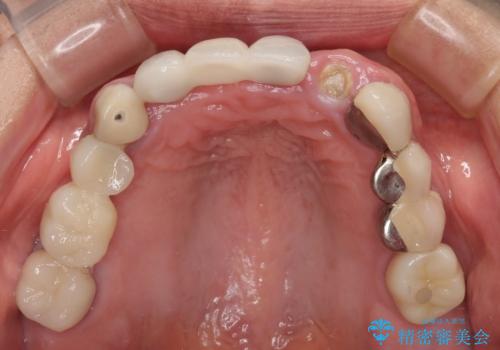

- 以前から頻繁に前歯が土台から外れてしまうことがあり、インプラントによる治療を希望して来院された患者様です。

歯根が割れていることはありませんでしたが、残っている歯質が全て歯肉よりも深い位置にあるため、土台としての機能は不足している状態でした。

歯根周辺の骨や歯肉の状態は良く、抜歯して速やかにインプラントを埋入し、即日で仮歯を装着するプランにて治療を行うこととしました。

事前に仮歯の型取りをして用意をしていたため、インプラント埋入後に速やかに仮歯を装着しました。

インプラントの安定度も高く、抜歯と埋入から2か月後にはオールセラミッククラウンを装着することができました。